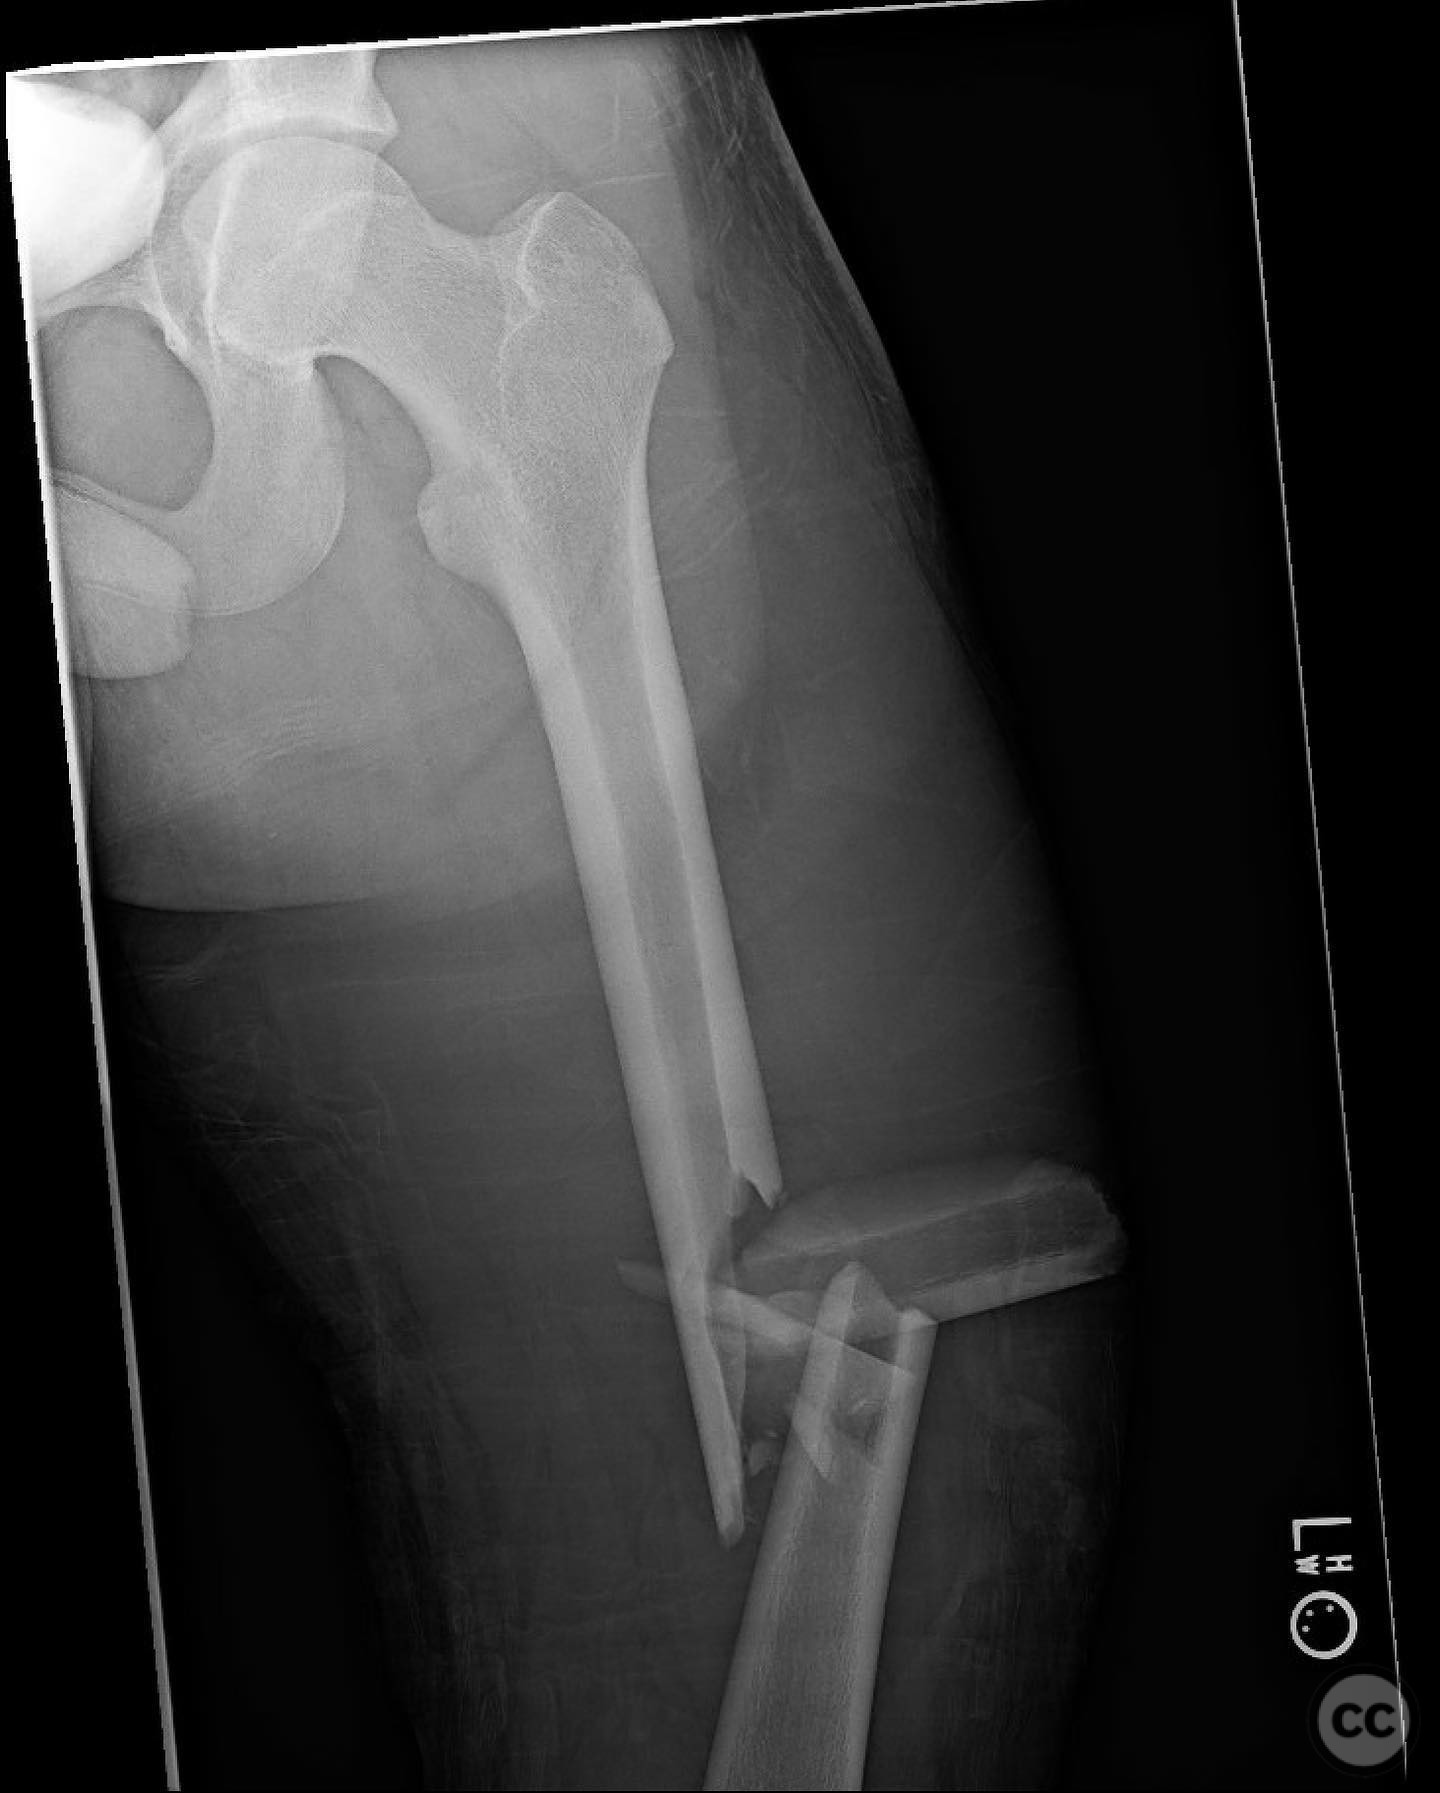

Comminuted Diaphyseal Femur Fracture in a 16-Year-Old

Clinical and radiological findings:  A 16-year-old male sustained a comminuted diaphyseal femur fracture after a 50-foot fall while rock climbing. The patient presented with multiple injuries but was well resuscitated and cleared for surgical treatment of the femur fracture within 24 hours. The injury was closed, with no neurological or vascular compromise noted.

Planning remarks:  The preoperative plan involved an open reduction and internal fixation (ORIF) due to the complexity of the fracture and the presence of a large incomplete napkin ring segment that could not be managed with closed nailing techniques. The anatomical approach was planned through a lateral incision to allow direct access to the fracture site for reduction and fixation.